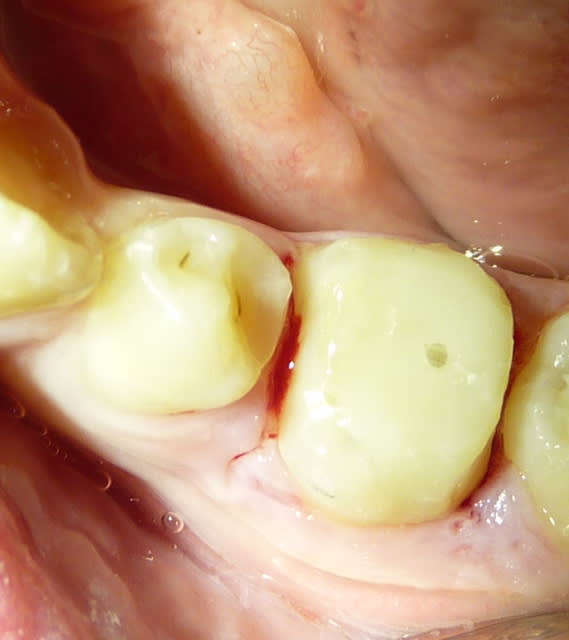

Qui ferait quoi dans le cas ci-dessous : 11 ans, patient en classe I, normodivergent, hygiène médiocre, très coopérant au fauteuil. 36 présente une carie similaire en lingual. Ces deux dents sont vitales.